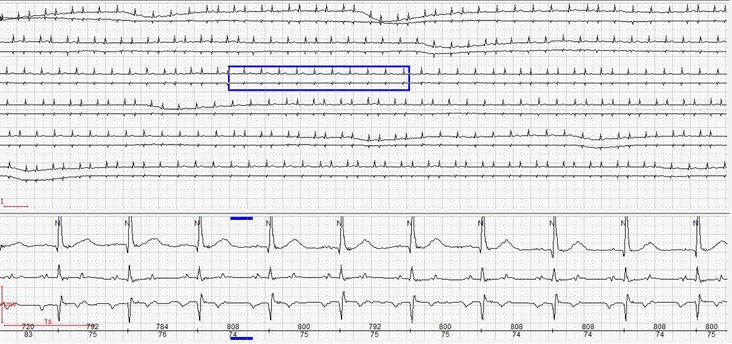

Holter ECG monitoring was performed which showed an incessant atrial tachycardia, periodically with an atrioventricular Wenckebach pattern (Fig. 3).

The P-R interval shows progressive prolongation until a ventricular pause occurs, occasionally with a 2:1 atrioventricular (AV) nodal conduction (Fig. 3.1). Such sequences indicate a Wenckebach AV nodal conduction mechanism. During the tachycardia, the QRS complexes were narrow (100-106 ms).

Fig. 3: Atrial tachycardia with atrioventricular Wenckebach pattern.

Fig 3.1: Wenckebach pattern with 2:1 atrioventricular nodal conduction.